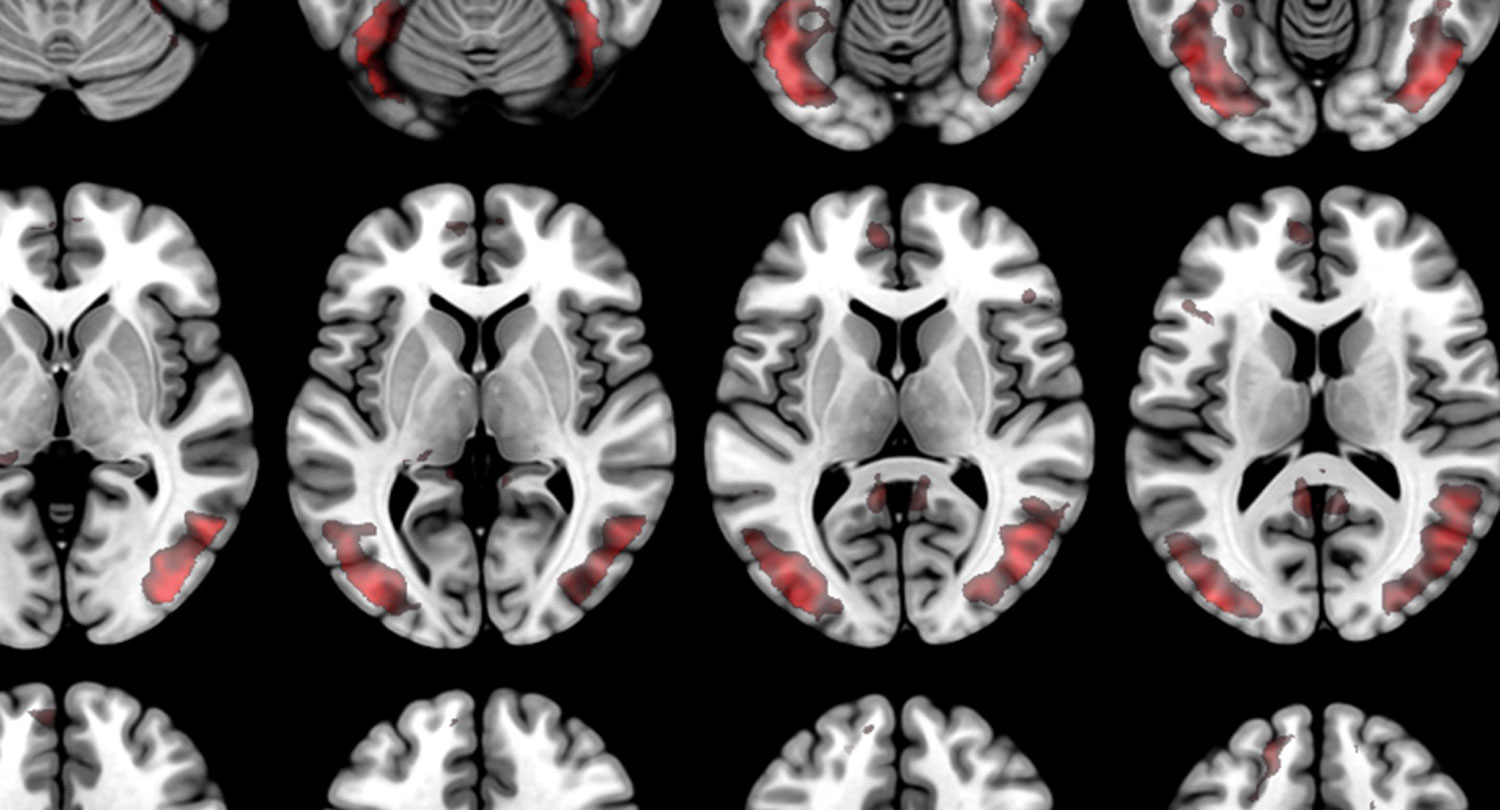

A Sharper Image

The McCausland Imaging Center boasts an MRI twice the strength of typical MRIsr